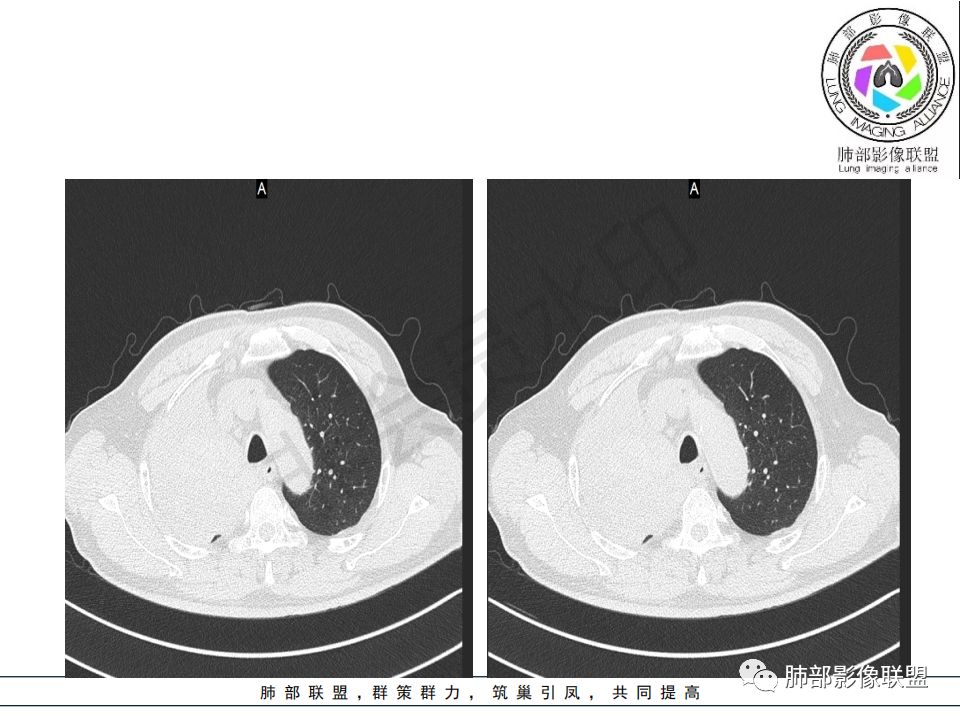

尘缘:

从强化情况和冠状位看主要还是从外向内的一个肿块,有不张,但不张范围不大,近端支气管堵塞,考虑腺癌或类癌(原发或转移都可能),鉴别鳞癌。

@曹坤,河北保定清苑区人民医院ct室 肿块大,阻塞和不张范围小,强化这么大肿块没有明显坏死,鳞癌这样相对少见了

@刘鋆(福州长乐区医院)影像科 转移啊,腔外都在生长,部分通过支气管壁进入腔内

@刘鋆(福州长乐区医院)影像科 先转移生长到外面,然后进入腔内生长,也是外朝内一种,与平时那种外朝内生长逐渐侵犯近端气管没有太多区别,只不过这个是转移而已。

病理结果:腺癌,考虑来源消化道

1.右肺上叶较大块影,密度不均,轻度强化并见低密度区,所属支气管截断并腔内突入,是符合肺鳞癌的影像学特征和生物学行为的。

2.胃癌常会首先胃旁淋巴结、腹主动脉淋巴结转移,肝脏血行转移,以及双肺多发转移,本例孤立右肺上叶病灶巨大,多有不符。

3.胃癌多血供,患者肺内病灶轻度强化。